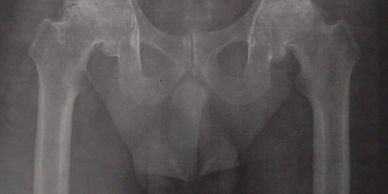

Artroplastía total de cadera izquierda

Paciente de 41 años, artrosis de cadera izquierda secundaria a necrosis ósea avascular (NOA). Se realizó una artroplastía total de cadera izquierda no cementada.